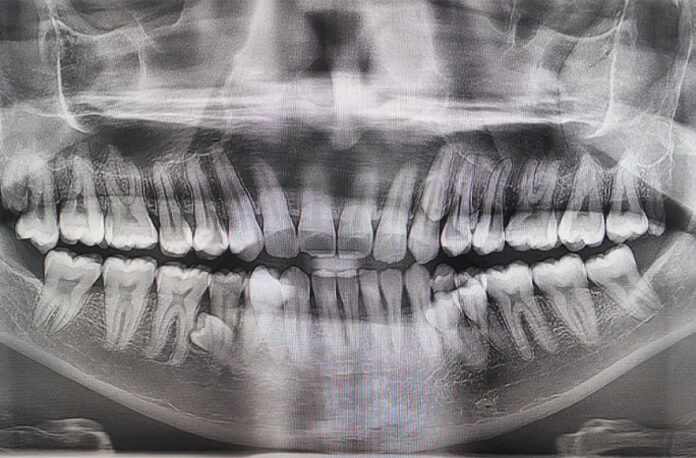

Наличие такого количества зубов подтвердили два стоматолога, которые обнаружили, что у него есть еще два непрорезавшихся. Пратаб Мунианди работает инженером в нефтегазовой отрасли и воспитывает сына. Рекордсмен рассказал, что впервые обратил внимание на зубы в 2021 году во время семейного чаепития. По словам Пратаба, тогда он пошутил с родными, что, похоже, у него растут дополнительные зубы. Вместе они решили их сосчитать и обнаружили 38. Впоследствии рентгеновское обследование показало, что в челюсти есть еще четыре зуба, которые на тот момент не прорезались. Отмечается, что зубы растут необычно, в два ряда.Рекордсмен заявил: «Это невероятное и особенное чувство знать, что я являюсь обладателем мирового рекорда по количеству зубов».-0-

Фото Guinness World Records